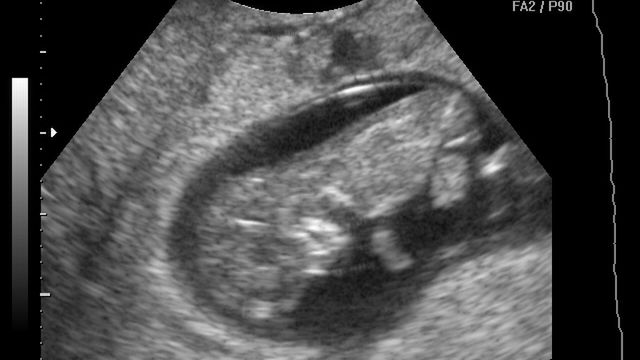

Płód w 10 tygodniu ciąży (zdjęcia)

W 10 tygodniu tworzą się palce u rąk dziecka, uszy oraz górna warga są już rozwinięte